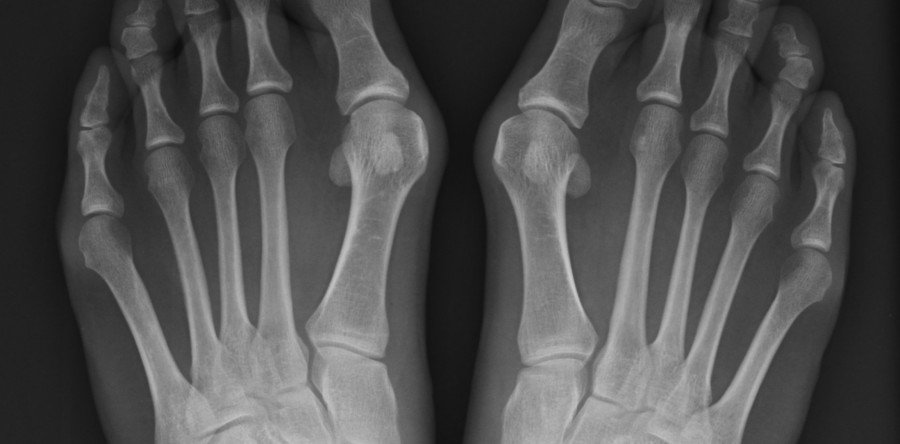

Alluce valgo – “cipolla” Per ALLUCE VALGO si intende una deformità dell’articolazione alla base dell’alluce, caratterizzata dallo spostamento verso l'esterno della base dell'alluce e dalla deviazione della punta dell'alluce stesso verso le altre dita. Questa patologia viene spesso indicata con il termine “cipolla”. L’alluce valgo, oltre a modificare l’anatomia del piede, può comportare: Dolore nella…